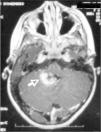

Se realiza resección subtotal del tumor, que resulta ser un astrocitoma pilocítico. La niña evoluciona bien postoperatoriamente, sin complicaciones posquirúrgicas en la TC de control, salvo resto tumoral no valorable con dicha técnica. Por esto, se realiza una RM meses después, que muestra recidiva local que ocupa el vermis inferior y el suelo del IV ventrículo, con extensión hacia hemisferio cerebeloso derecho (fig. 2).